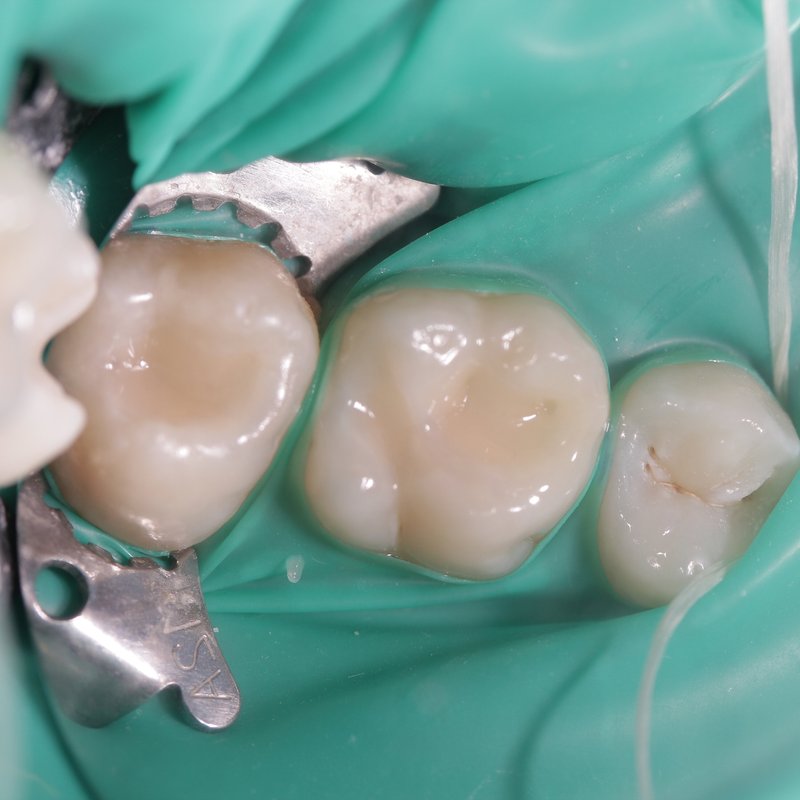

Фотогалерея